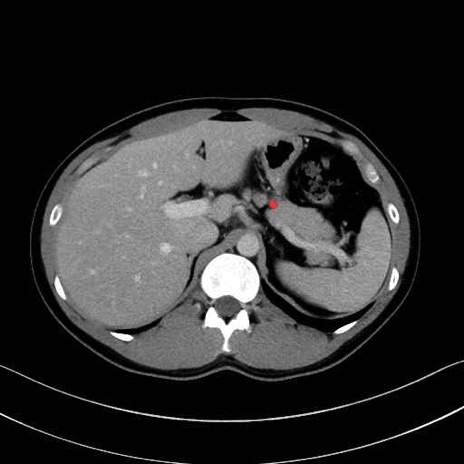

【症例】20歳代 男性 スクリーニング

■起始:典型的には腹腔動脈幹(celiac trunk)から左胃動脈・総肝動脈とともに三分岐し、脾動脈は左後上方へ向かう。

■走行:膵上縁または膵実質背側を蛇行しながら左方へ進み、膵尾部近傍で脾門へ至る。蛇行の程度は個体差が大きい。

■終枝:脾門部で複数の終末枝に分かれ、上極・下極枝や脾門枝群を形成する。胃短動脈群や左胃大網動脈はしばしば脾動脈から分岐する。